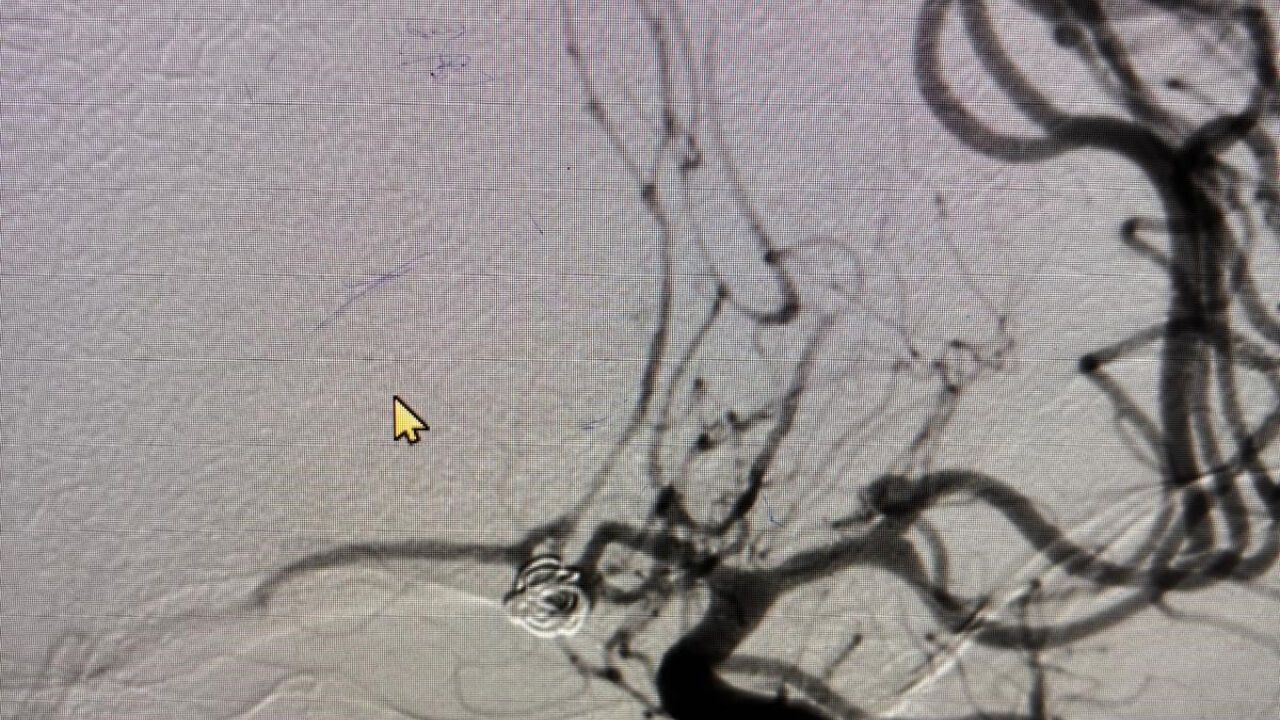

Prof. Dr. Aytaç, beyin baloncuğunun patlaması halinde hastaların büyük bir kısmının hayatını kaybettiğini ifade etti. "Kanama olan hastaların yüzde 10’u hemen hayatını kaybederken, kalan yüzde 50’si ise bir ay içerisinde hayatını kaybetmektedir. Bu hastalık çok ölümcül seyreden bir rahatsızlıktır," diye belirtti. Beyin baloncuğu tespit edildiğinde ise, baloncuğun kapatılması ya da cerrahi müdahale ile baloncuğun ortadan kaldırılması gerektiğini söyledi. Kasıktan girerek yapılan tedavi yöntemlerinin, hastaların hayatını kurtarma açısından önemli olduğunu ekledi.